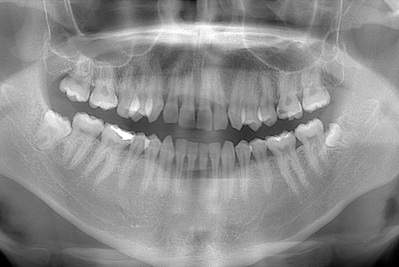

定期検診ではクリーニングのみではなく、経過観察歯のチェックや古くなってきた詰め物・被せ物のチェックなども合わせて行います。1年に1度お口全体のレントゲンをお取りさせて頂き目に見えない虫歯の確認や歯周病による骨吸収の有無をみています。

お口の中の病気はレントゲン写真検査を行わないと診断が難しいものが多くあります。直接見えない部分を把握するためにレントゲン撮影をさせて頂きます。

お口の中の病気はレントゲン写真検査を行わないと診断が難しいものが多くあります。

定期検診の場合約1〜2年に1回ほど、もしくは歯科医師・歯科衛生士の判断で必要な場合撮ることがあります。